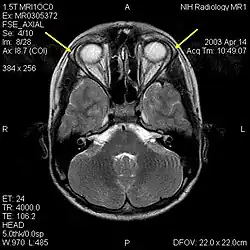

| MRI of the brain of 12-year-old boy with triple-A syndrome showing hypoplastic lacrimal glands (yellow arrows) | |

The diagnosis of this condition involves examination by a health provider. Clinical signs may lead to the diagnosis such as the lack of tears and digestive issues, such as acid reflux disease in infancy as well as symptoms of adrenal insufficiency such as frequent bouts of low blood sugars are highly suggestive of the disorder.[7][5][9] Achalasia may be seen on plain X-rays and include an absence of fundal gas shadow, widened mediastinum and an air fluid level in mediastinum is also seen. The gold standard for confirming achalasia is a 24 hours manometry of oesophagus.This is a test that measures the pressure inside the esophagus. The test demonstrates non-relaxation of lower esophageal sphincter, increased tone of esophageal sphincter, atonic esophagus. Bird-beak sign and rat-tail sign can be appreciated on barium swallow.[17][18][19] Lack of tears or alacrima is caused by the lack of production of lacrimal glands or ducts and defects in the nerves of the lacrimal gland caused by a dysfunction in the autonomic nervous system.[20] The diagnosis is confirmed with genetic testing as well as clinical features.[9]